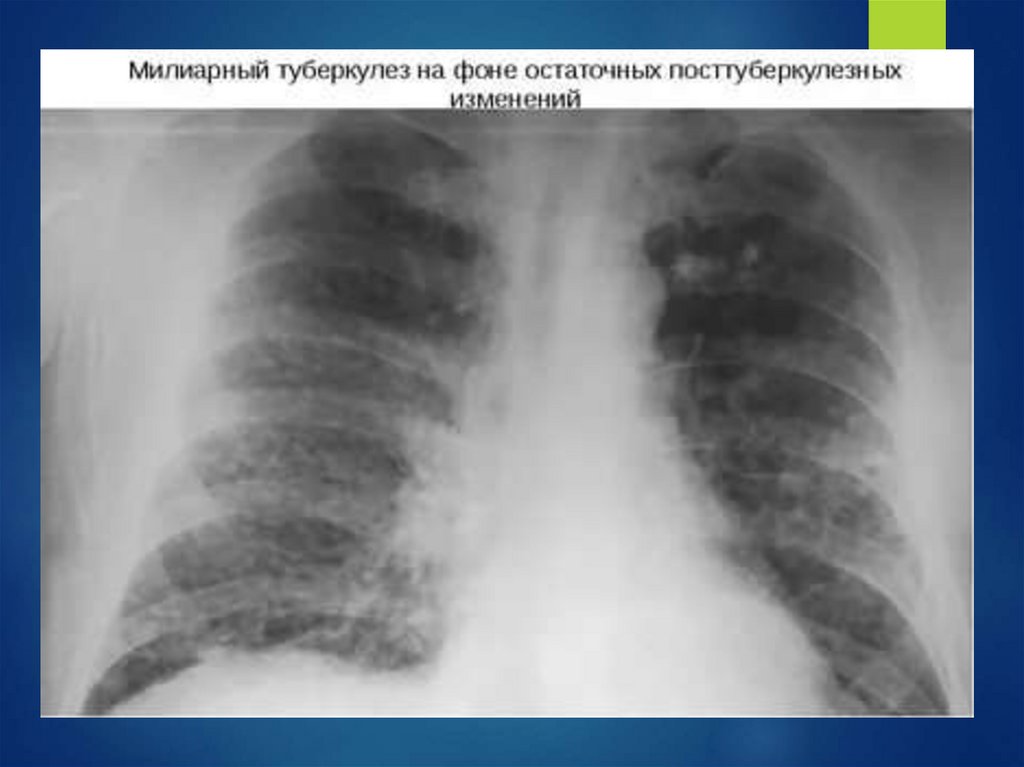

СИНДРОМ ГУДПАСЧЕРА